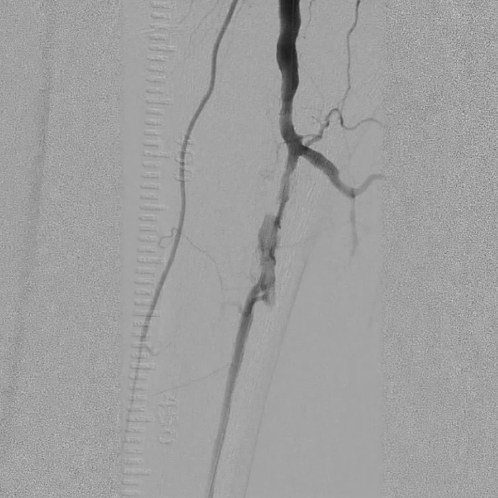

球囊预扩张与病变处理

选用2×40mm普通球囊扩张闭塞病变,造影可见局部内膜撕裂严重,形成明显夹层(提示病变坚硬,需支架支撑)。